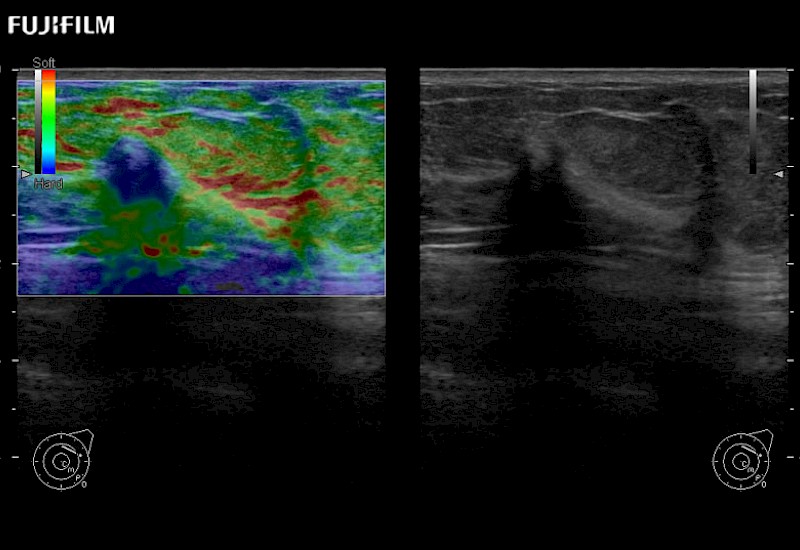

Multi-Parametric imaging modalities

Our dedication to Surgical Oncology allows us to offer superior image quality, outstanding system reliability and intuitive use of cutting edge technology.

- Instant feedback on tumor margin delineation

- Valuable information to guide tumor resections

The ARIETTA 750 incorporates all of the proven technologies and functions that medical professionals have come to expect from Fujifilm Healthcare.

ARIETTA 750 is the definitive diagnostic ultrasound solution for any clinical setting - Private Office, Imaging Center, or Hospital. The ARIETTA platform provides the ultimate in clinical performance with its state-of-the-art features and large user-friendly display.

The ARIETTA 650 DI combines trusted Fujifilm Healthcare technologies and features tailored for surgical oncology.

Designed to meet the demands of surgeons, the ARIETTA 650 DI offers precise guidance. Its advanced capabilities and large, intuitive display offer accurate and efficient care in operating rooms and specialized surgical settings.

Fujifilm Healthcare continues to listen to the experts, our neurosurgeons, by developing an ultrasound system specifically designed for the Operating Room.

Guidance is the fundamental purpose for all of our surgical ultrasound technology. Fujifilm Healthcare is committed to designing tools that help neurosurgeons navigate inside the human body and provide the necessary information to immediately make critical surgical decisions.

With the ARIETTA Precision the next level of surgical ultrasound is here.